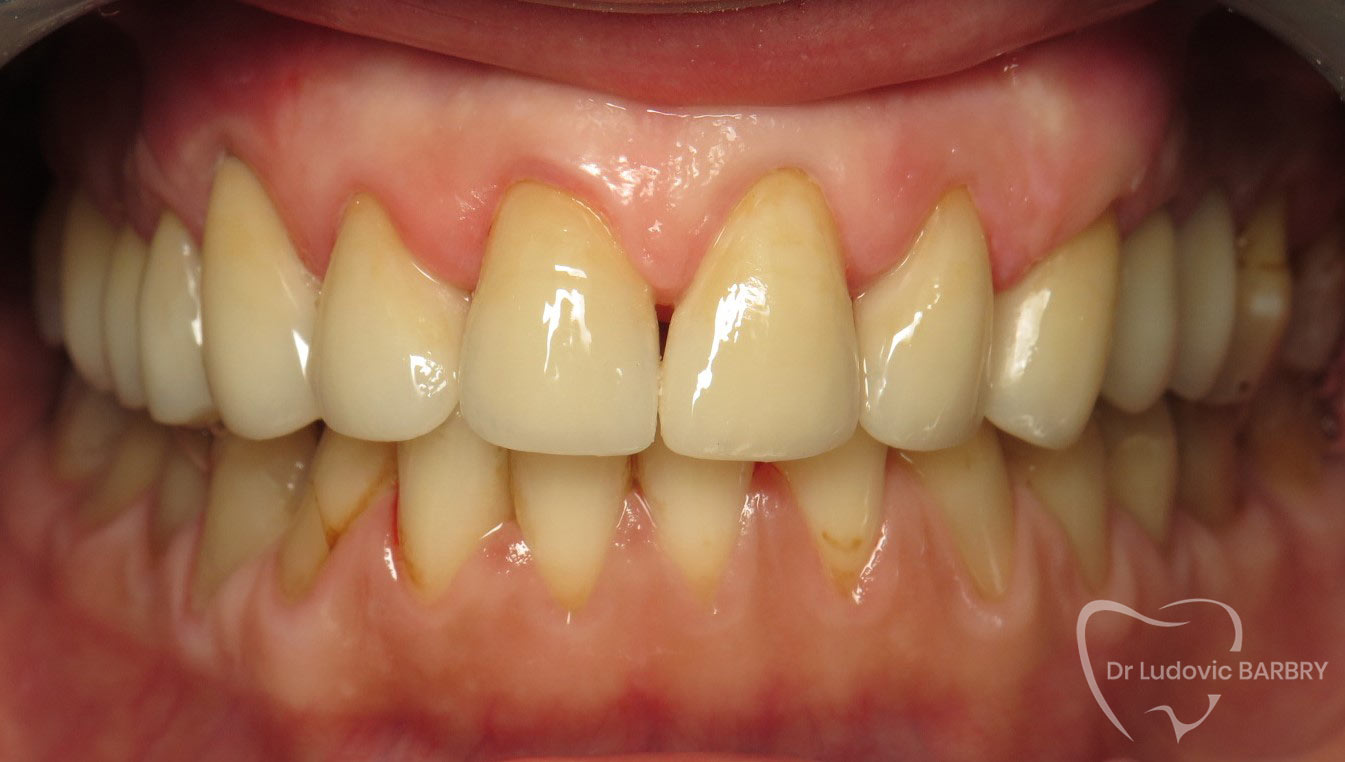

Progressivement la plaque dentaire se minéralise, en incorporant des sels de phosphate de calcium de la salive. Ceci donne naissance au tartre.

Le tartre n’est pas naturellement coloré. Son état de surface favorise également l’accumulation des colorations inesthétiques du café, thé, tabac…

Seul votre chirurgien-dentiste pourra l’éliminer le tartre grâce au détartrage, et les coloration grâce à un aéropolissage.